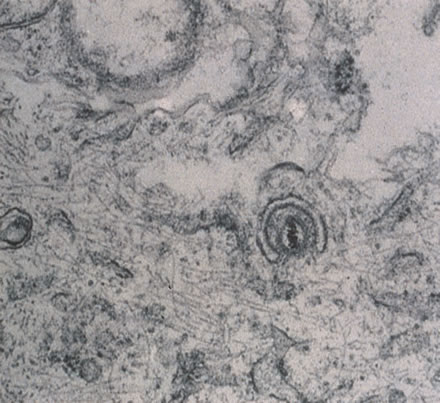

HIV was previously known as human, T-cell lymphotropic virus type 3 (HTLV-III) and lymphadenopathy-associated virus (LAV). There are two known types of virus: HIV type 1, which causes AIDS, and HIV type 2, the disease spectrum of which is uncertain. HIV type 2 has been found in some African cases of AIDS. HIV is a retrovirus, meaning it contains a reverse transcriptase enzyme that produces a double-stranded DNA copy (cDNA) from the virus RNA genome (Fig. 9).24 HIV infection involves attachment of viral envelope glycoprotein to the CD4 molecule present on T-helper (T4, OKT4, or CD4+) cell surfaces. The virus then fuses with the cell membrane, enters cytoplasm, loses its envelope, and reverse transcription of RNA to DNA occurs. Viral DNA becomes integrated into host cell DNA as latent provirus, in which state it may go unrecognized by the immune system. The proviral DNA can then be transcribed and translated, producing viral proteins and viral genome RNA, which assemble and bud through the host cell plasma membrane as new virions. Antigenic stimulation of lymphocyte activity appears to be important in conversion from latency to progressive infection.

Fig. 9. An electron micrograph of the human immunodeficiency virus type 1 (HIV-1) in the retina.